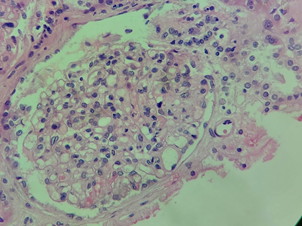

A skin biopsy was performed with IgM and C3 deposits associated with thrombocytopenia, bilirubin elevation, and acute renal failure, and the condition was compatible with aHUS Figure 1–5. Treatment with Intravenous Immune Globulin (IVIG) and Dexamethasone was started from 08/24 to 08/29/2023 and Eculizumab was started on 08/25/2023. A patient with prolonged hospitalization for three months, diagnosed with rare diseases, developed pulmonary thromboembolism, deep vein thrombosis of the right lower limb, and was anticoagulated with Apixaban. He was discharged and one month after discharge, he recovered his kidney function, using Ecolizumab, no longer requiring hemodialysis, in addition to the exchange of Apixabana for Marevan.

Figure 1 Biopsy - acute kidney failure - acute tubular necrosis I.

Kidney biopsy (August/2023)

Severe acute tubular necrosis.

Immunofluorescence negative for all antisera investigated.